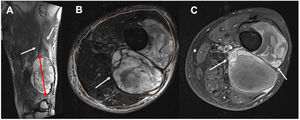

El primer radiólogo (R1) determinó las siguientes características morfológicas de cada TPB. Tamaño: mayor diámetro en cm, medido en las secuencias sensibles al líquido. Profundidad: localización superficial o profunda relacionada con la fascia muscular periférica profunda, determinada en la secuencia axial T2 turbo spin-echo (TSE). Edema perilesional: zonas hiperintensas que sobrepasan el margen de la lesión en las secuencias sensibles al líquido. Realce nodular periférico: focos redondeados (mayores de 2mm) de captación de contraste en la secuencia T1 FS posterior a la inyección de gadolinio en los límites de la lesión. Heterogeneidad de la lesión en T2 TSE: al menos un tercio del área con cambios en la intensidad de la señal. Zonas de necrosis quística: focos hipointensos de al menos 2mm, sin realce en T1 FS posgadolinio (fig. 1).

Figura 1.Determinación de las características morfológicas de los TPB en un sarcoma pleomórfico indiferenciado en una mujer de 56años. A)Medición del eje largo (línea roja) y determinación del edema perilesional (flechas blancas) en una T2 FS coronal. B)Tumor profundo (flecha blanca) según la relación con la fascia superficial (puntos naranjas), y lesión heterogénea con al menos un tercio del área con cambios en la intensidad de la señal. C)Realce de focos nodulares periféricos (flechas blancas) en T1 FS posgadolinio, y zonas de necrosis quística: focos hipointensos de al menos 2mm, sin realce en T1 FS posgadolinio (flechas negras).